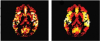

Partial volume correction using modified least trimmed squares (PVC-mLTS) is a software toolbox that can be employed to correct partial volume effect for single inversion-time ASL data.

(3) Applying mLTS to ASL data for correcting partial volume effect

(3) Computing CBF maps for both GM and WM.